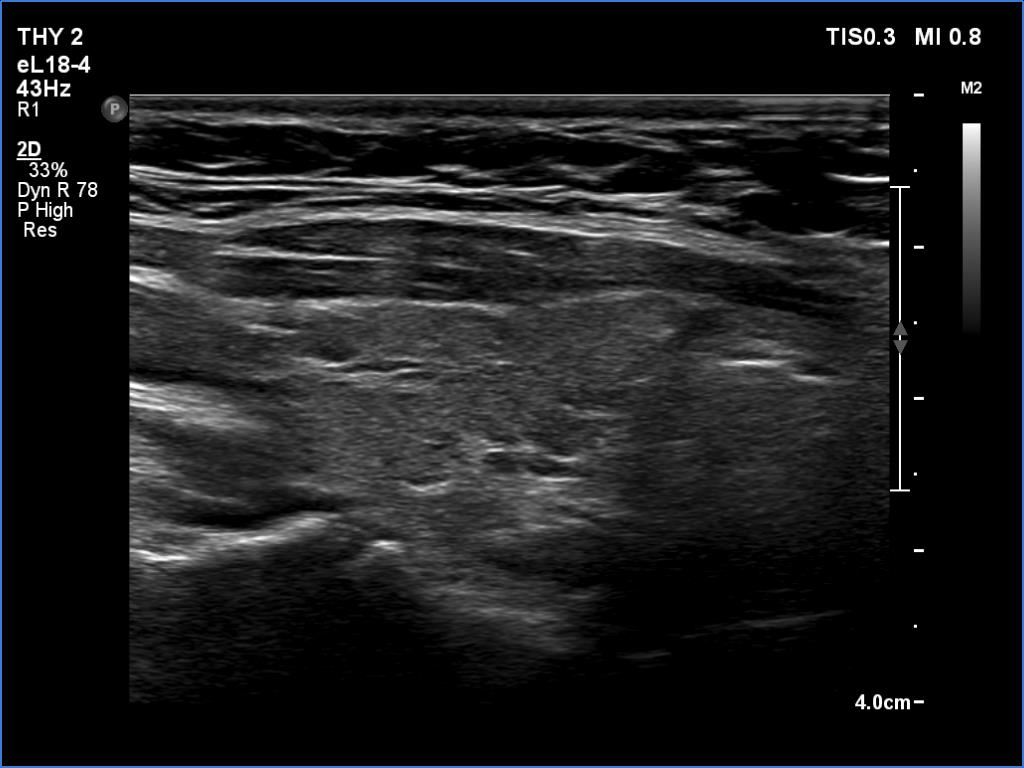

Lymphocytic thyroiditis - case 188 (ultrasonographic picture 4)

Right lobe, longitudinal scan

Right lobe, longitudinal scan - set to higher level of harmonization.